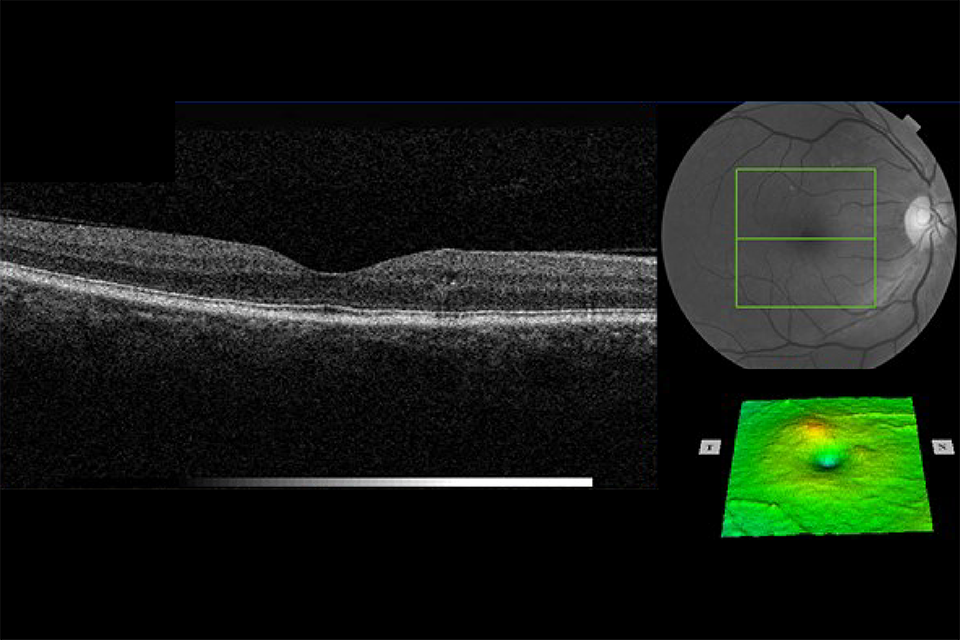

OCT retina images Example 7 R1M1 and OCT positive

Example 7 has an area of retinal thickening greater than 1/2 disc area, the edge of which is within 1 DD of the central fovea. It has:

- photographic surrogate markers for M1

- intraretinal cysts

- no change in foveal contour

- retinal thickening (more than 1/2 DA) the edge of which is within 1 DD of the central fovea

Outcome: referral to HES (unless extenuating circumstances requested by clinical lead).